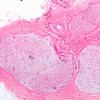

PERIPHERAL NEUROPATHY

11 VASCULITIS - VASCULOPATHY

2 Vasculopathy (3)